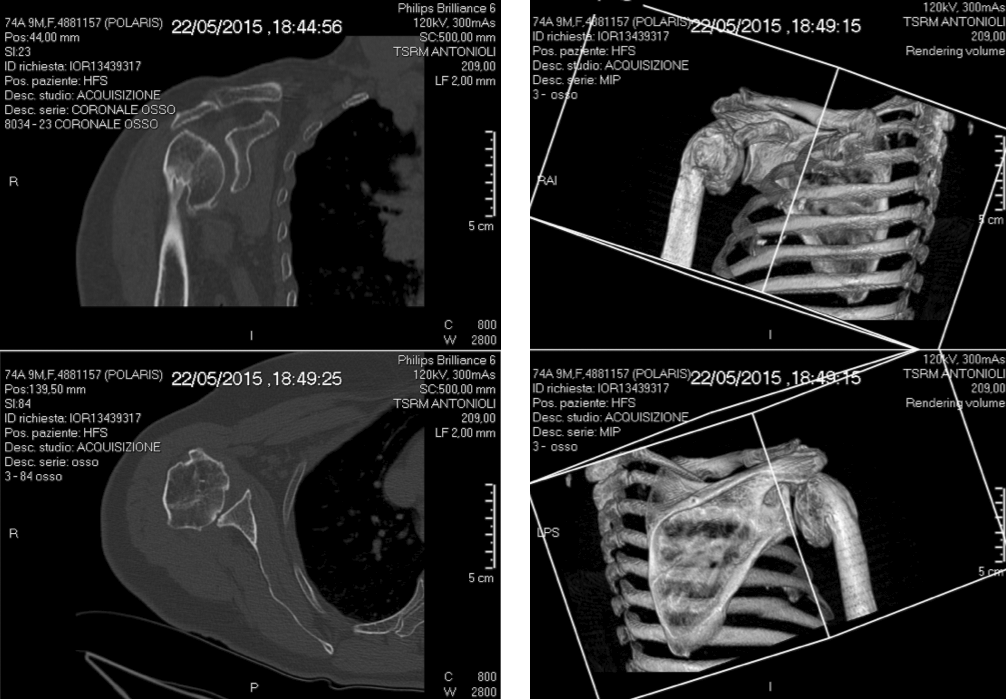

Pre-op

- Sequelae of proximal humerus fracture, treated with plate and screws in 2001

- New right shoulder fracture, treated conservatively in 2008

- Now in severe pain

- Elevation 40°, abduction 30°, very low rotation

- Deltoid muscle can be activated